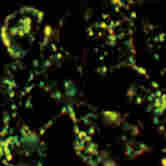

圖3:近紅外二區(qū)顯微細胞成像

- 生物醫(yī)學研究:在腫瘤檢測與治療研究中,它可以幫助我們實時監(jiān)測腫瘤的生長、轉(zhuǎn)移和對治療的響應,為個性化治療方案的制定提供依據(jù)。在神經(jīng)科學領(lǐng)域,能夠觀察神經(jīng)信號的傳遞和神經(jīng)網(wǎng)絡的活動,為神經(jīng)系統(tǒng)疾病的研究和治療開辟新的途徑。此外,在心血管疾病、免疫學等方面,也能發(fā)揮重要作用,助力科學家們攻克一個個醫(yī)學難題。

- 成像清晰度高:有效減少了光散射和吸收的干擾,讓我們看到的微觀世界更加清晰、細膩,不放過任何一個細節(jié)。在腫瘤研究中,能夠清晰地分辨腫瘤細胞與正常細胞的邊界,為腫瘤的早期診斷和治療提供有力支持。